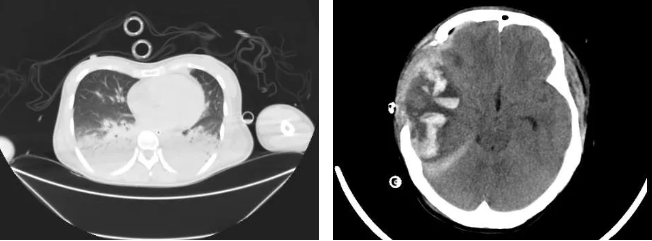

重型颅脑损伤是一种极其严重的创伤,其死亡率和致残率在全身创伤中均居第一位;应激性心肌病是种由强烈的身体或心理应激引起的可逆性心功能障碍,可导致心功能急剧下降,甚至危及生命。当这两种严重疾病状态同时出现在一位患者身上时,治疗的难度和风险可想而知。

患者 “外伤后意识不清2天”从当地医院紧急转入郑州大学第五附属医院,入院时患者深昏迷,在大剂量升压药物和呼吸机辅助呼吸条件下,生命仍危在旦夕。ICU 团队迅速行动,通过详细的检查和分析,很快明确了重型颅脑损伤合并应激性心肌病的诊断。